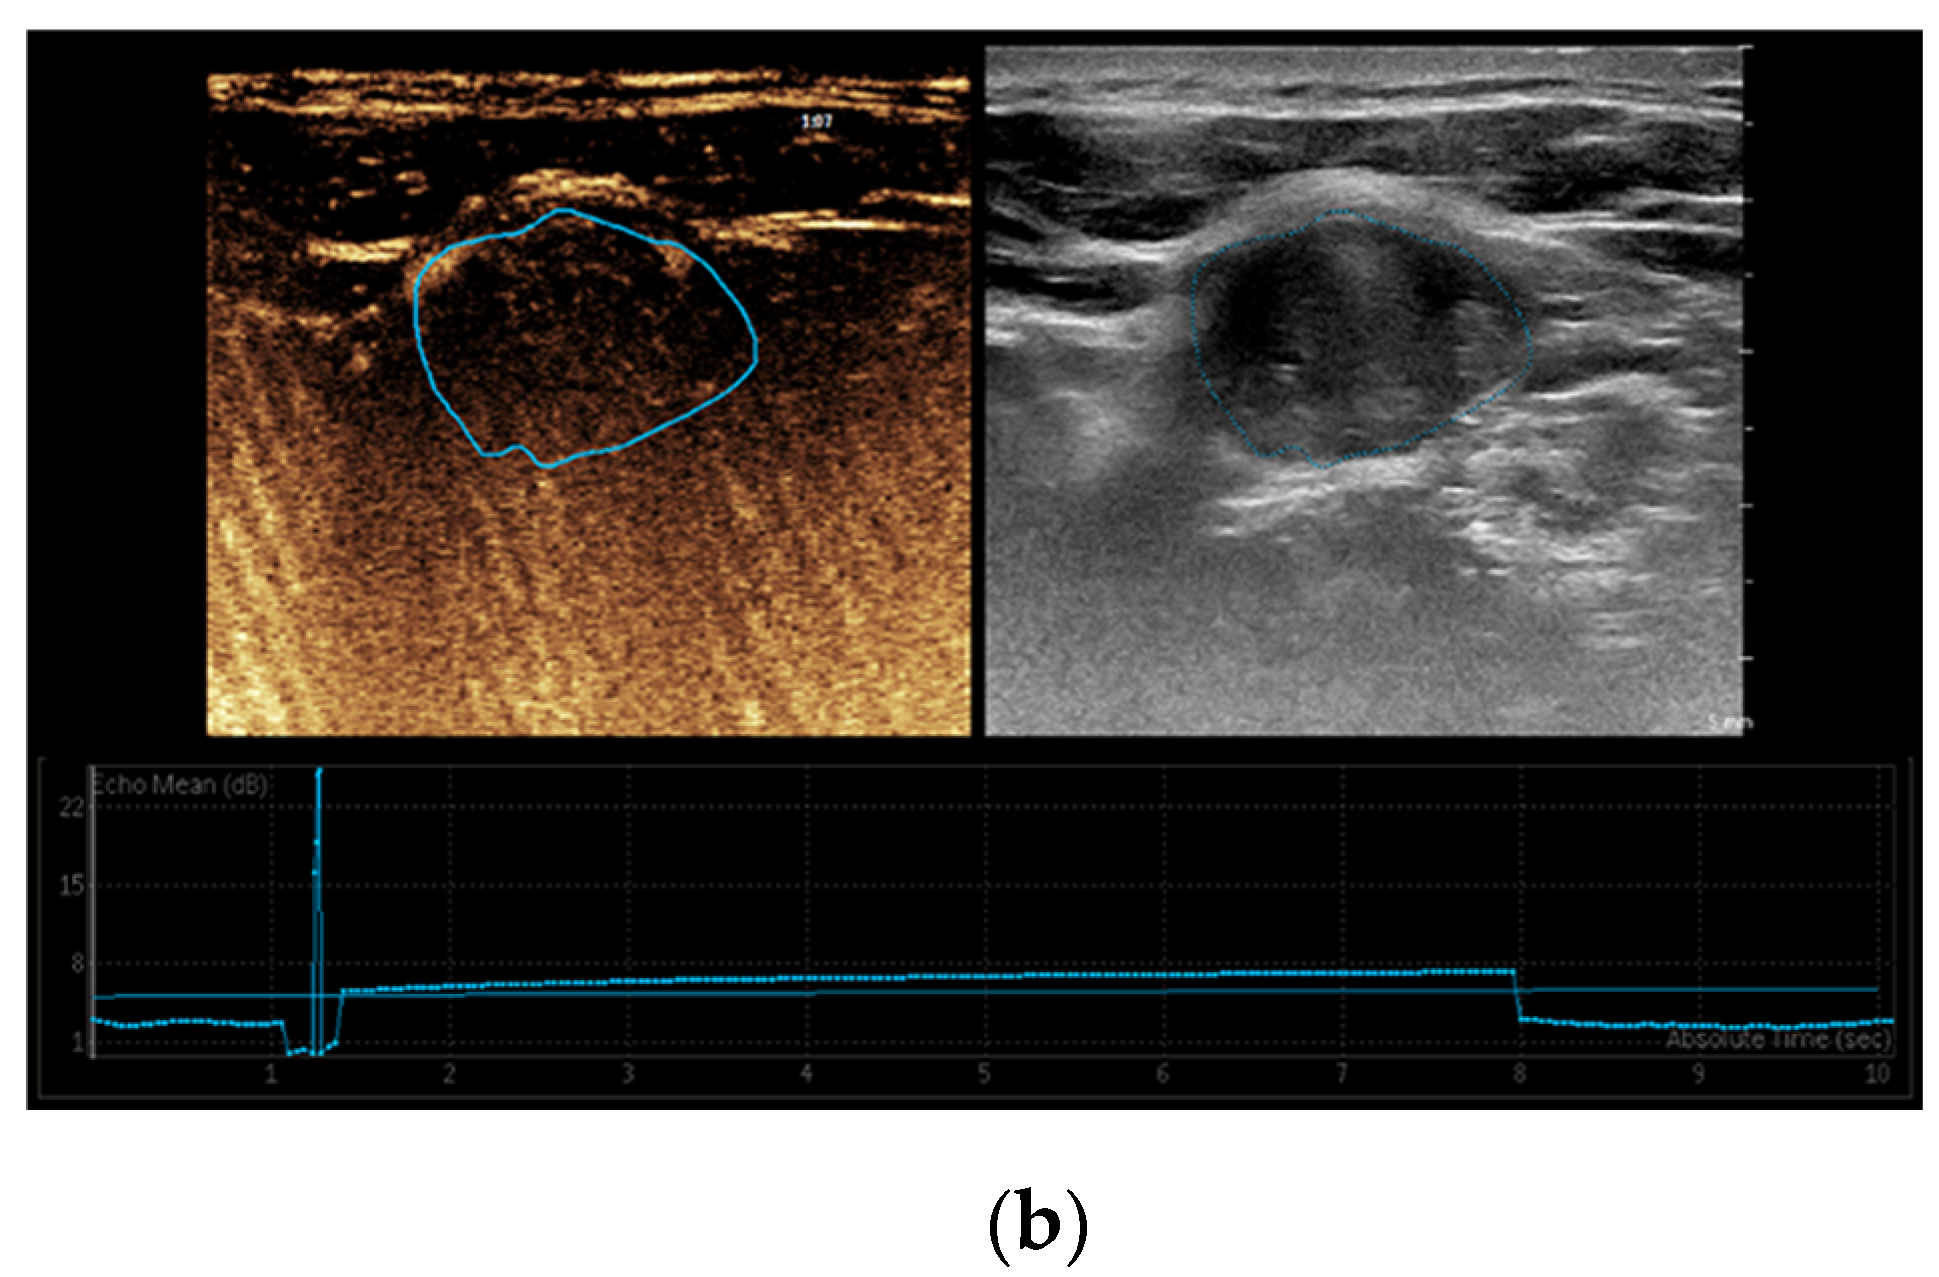

3.1. Elastography

3.2. CEUS